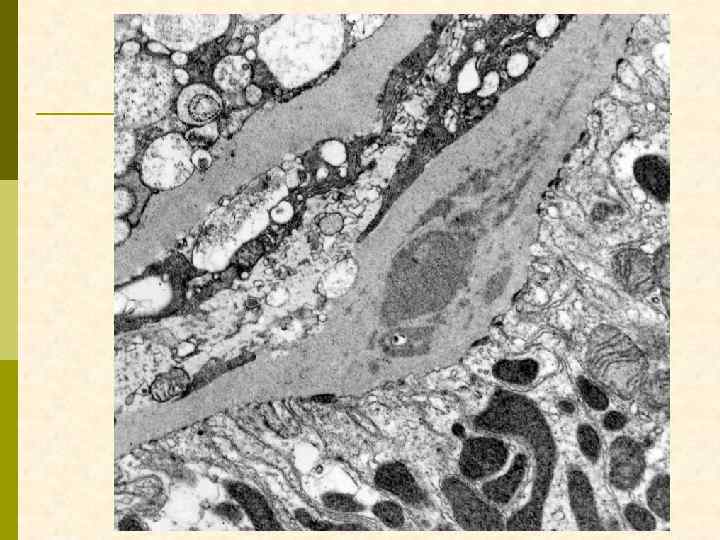

Характерные морфологические признаки ВИЧАН p почки больших размеров p тяжелое повреждение клубочков – коллаптоидный вариант ФСГС p расширение мезангия p гиперплазия и пролиферация подоцитов, аномалия висцерального и париетального эпителия клубочков – дедифференцирование ? ? ? p иммунные депозиты минимальны p атрофия канальцевого эпителия, кистозная дегенерация канальцев с заполнением их белковыми цилиндрами p нередкий тяжелый интерстициальный отек с моноцитарной (лимфоцитарной) инфильтрацией p нередко острый канальцевый некроз p ЭМ: тубуло-ретикулярные структуры в эндотелиоцитах клубочковых капилляров и других сосудов

атрофия канальцев, умеренная инфильтрация интерстиция

Заключение по ЭМ p В нефробиоптате один частично склерозированный клубочек со значительно утолщенной капсулой, в которой имеются массивные отложения электронно-плотных депозитов и скопления коллагеновых волокон. В неизмененных зонах клубочка гломерулярная базальная мембрана (ГБМ) капилляров неравномерно утолщена с интрамембранной локализацией электронноплотных депозитов. Субэпителиальных и субэндотелиальных депозитов мало. Более массивные депозиты расположены в умеренно расширенном мезангиальном матриксе. В ГБМ коллабированных капилляров обнаружены депозиты смешанного характера с микролипидными включениями. Цитоплазма подоцитов с умеренным набуханием при незначительной микроворсинчатой трансформацией и со слияние малых ножек. HIV-ассоциированные тубулоретикулярные включения обнаружены в цитоплазме многих эндотелиальных клеток гломерулярных капилляров.